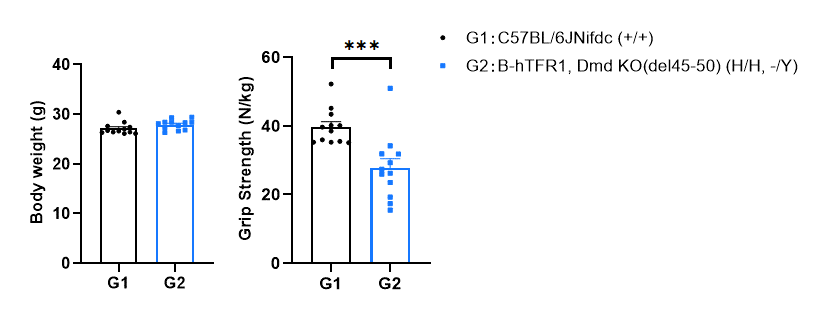

Behavioral performance in wild-type C57BL/6JNifdc and homozygous B-hTFR1, Dmd KO(del45-50) mice. Grip strength tests were conducted to assay the behavioral performance in wild-type C57BL/6JNifdc and homozygous B-hTFR1, Dmd KO(del45-50) mice (male, 3-month-old, n=12). Grip strength results showed the strength produced by forelimb was ~27.8 N/kg in homozygous B-hTFR1, Dmd KO(del45-50) mice, which was significant weaker than that in wild-type control mice. All grip strength measurements are normalized to the individual animal’s body weight. Values are expressed as mean ± SEM. Significance was determined by unpaired t test. *P < 0.05, **P < 0.01, ***P < 0.001, ****P < 0.0001.